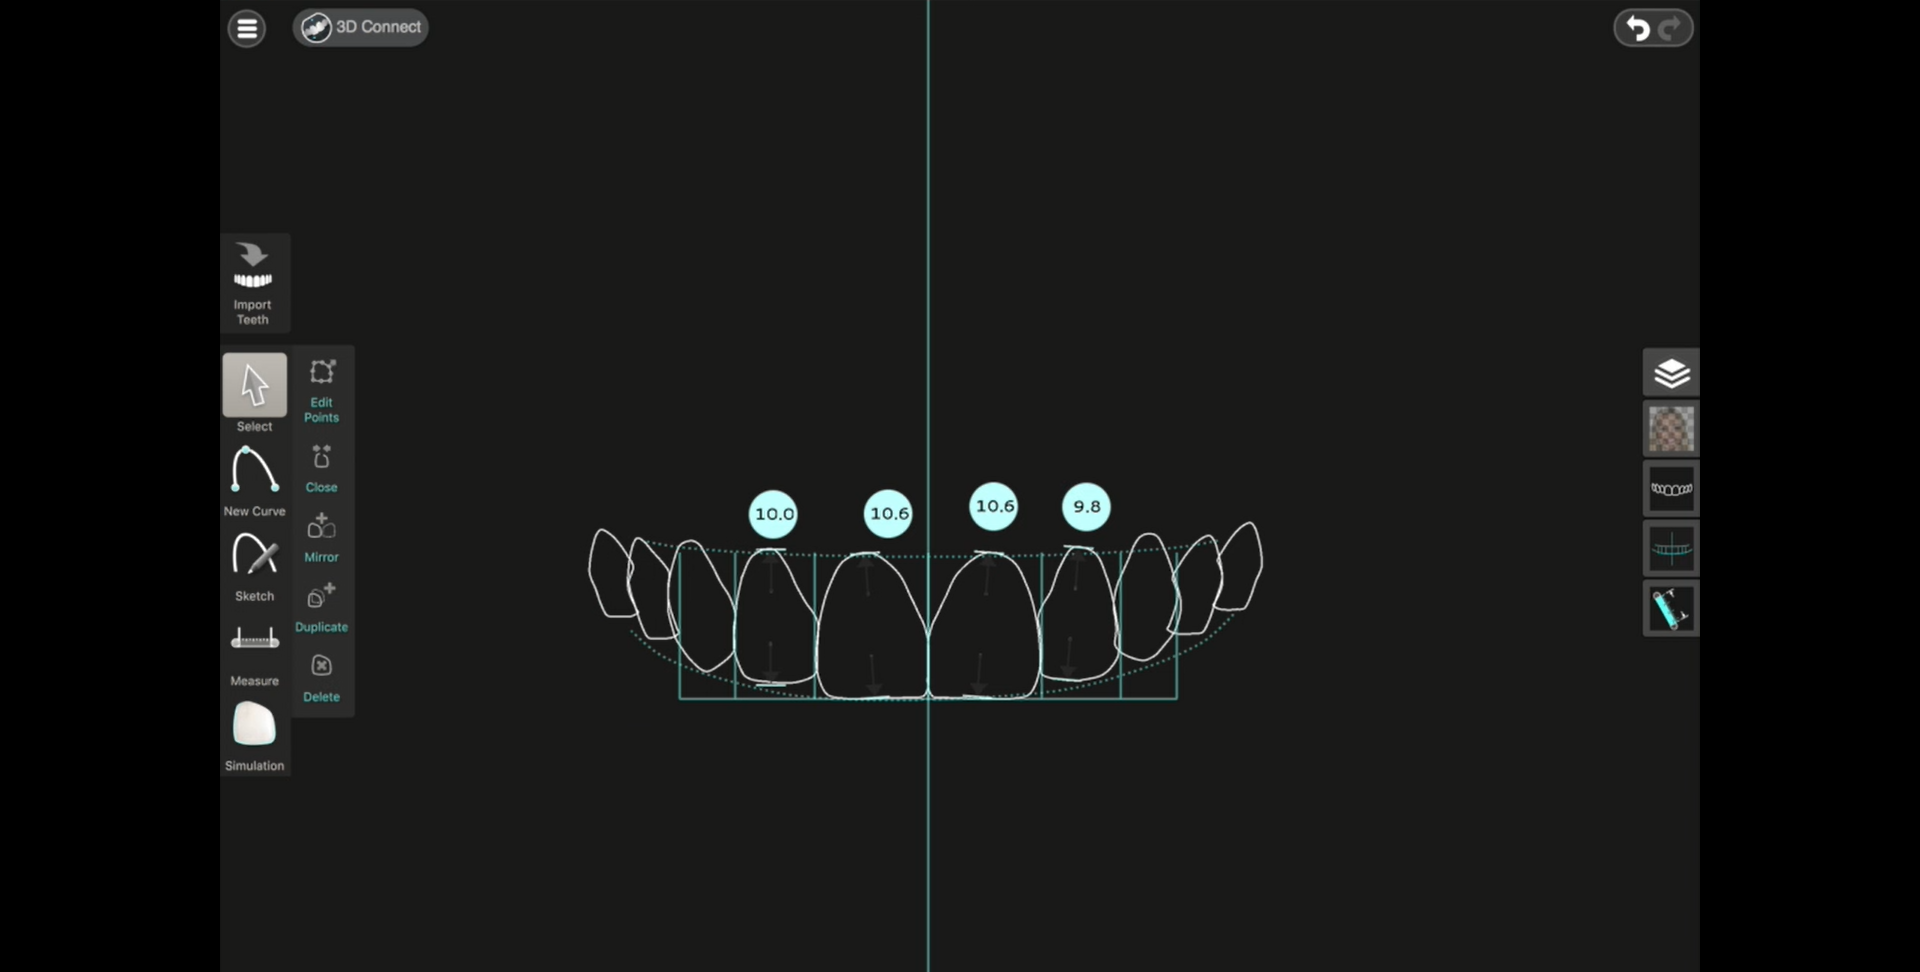

Belirlenen yeni diş yapısı ve dental oranlara göre gülüş tasarım yazılımı, planlanan tedavinin bitmiş halinin sanal görüntüsünü oluşturur. Bu görüntü üzerinde, hastanın da istek ve düşünceleri dikkate alınarak gerekli düzeltmeler yapılır.

Son hali verilen dijital gülüş tasarımı üzerinde dijital ölçümler yapılarak veya doğrudan Cad-Cam cihazlar kullanılarak dijital planlama , Mock-up adı verilen reel tasarıma dönüştürülür. Daha sonra, Mock-up tasarım, ağıza aktarılarak geçici dişler üretilir. Bu aşamada , yüz-dudak ve alt-üst dişlerin birbirleriyle uyumları ile diş renk ve boyutları, dişeti konturları detaylı olarak tekrar değerlendirilir. Bu değerlendirmeler sonrasında Mock-up üzerinde gerekli son düzenlemeler yapılıp protetik işlemlere geçilir. Bu iş akışı neticesinde elde edilen estetik sonuç, dijital tasarım ve Mock-up çalışması ile oldukça uyumludur.